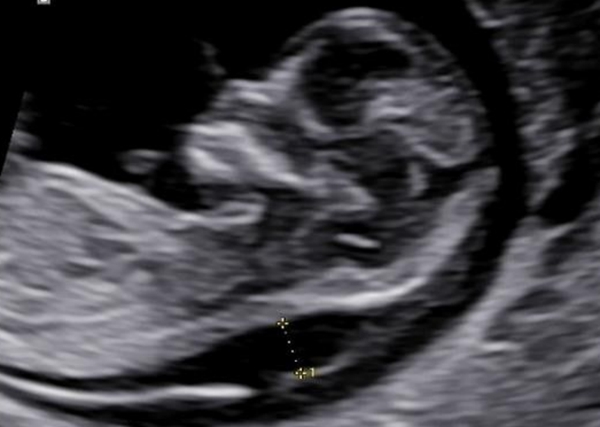

終于,屏幕上的細(xì)微線索被一一捕捉、放大并深入分析。許燕主任團(tuán)隊(duì)發(fā)現(xiàn),這并非簡單的NT增厚,在胎兒頸背部皮下還清晰可見網(wǎng)格樣回聲——這是典型的頸背部水囊瘤樣表現(xiàn),與單純的NT增厚性質(zhì)截然不同,這意味著胎兒可能存在更為復(fù)雜的健康問題。